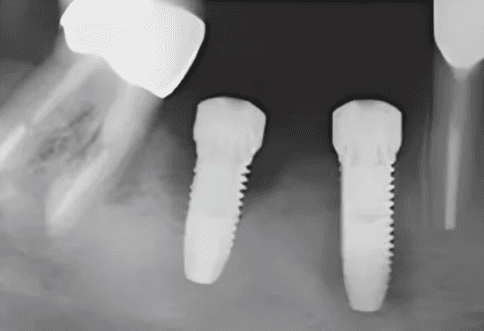

A friend told me that she placed implants at 18 and 19, and they failed. Then she had gone back to remove them, meticulously clean and graft, and then she had placed 2 new ones at that same site.

And then, lo and behold, they failed again!